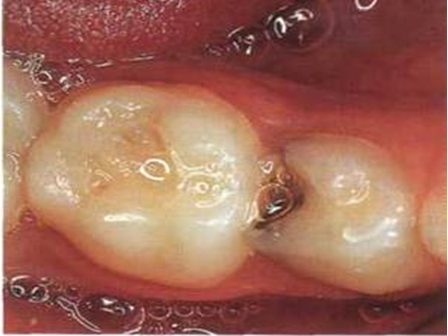

Poseban problem predstavlja topljenje zuba na bočnim površinama koje su u međusobnom kontaktu. Proces topljenja se tu odvija neprimetno, uglavnom nema bilo kakvih simptoma, poput osetljivosti(mlečni zubi su slabije osteljivi, ali i kod stalnih obično ide bez simptoma). Kada zubna gleđ dovoljno oslabi, prilikom najobičnijih pokreta žvakanja dolazi do pucanja zuba i lezija postaje vidljiva.(Slika 2.). I to izgleda kao da je „potpuno zdrav zub preko noći oboleo“.

Slika 2. Pucanje zuba posle dužeg topljenja zubne gleđi na bočnoj površini. Velika je verovatnoća da je kod ovakvog defekta već došlo do nepovratne infekcije inutrašnjosti zuba(zubna pulpa, “živac”)